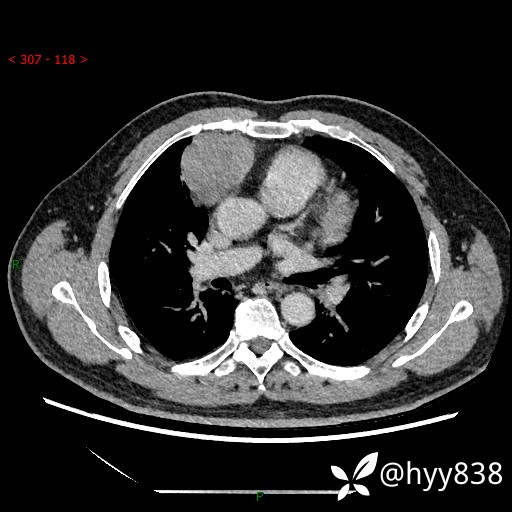

动脉期+静脉期